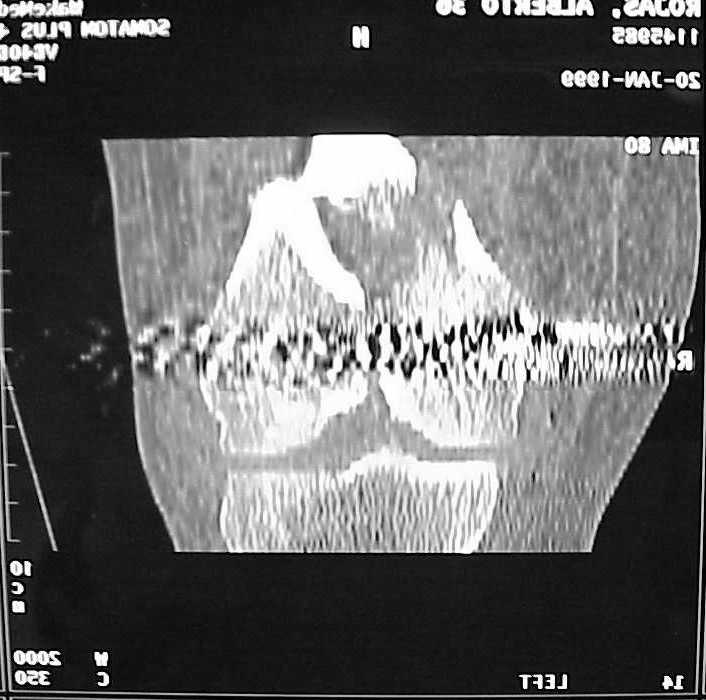

Use 6.5 mm cannulated screws if you have and

place one anterior to where IMN will go if anterior cortex if insufficient and AP screws on either side of the IMN out of the trochlea to provide some additional varus/valgus stability. I worry about the leg going into valgus w/the lack of lateral cortex.

See attached case that was done several years ago before LISS. He had comminuted trochlea and anterior blocking screws were used to prevent anterior IMN cut-out.